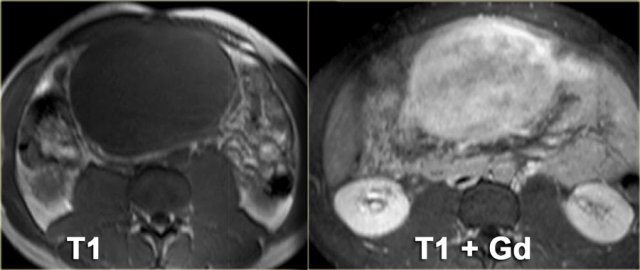

Peritoneal inclusion cyst (3)

On the left another example of a peritoneal inclusion cyst.

There is a nice correlation between the MR and the specimen.